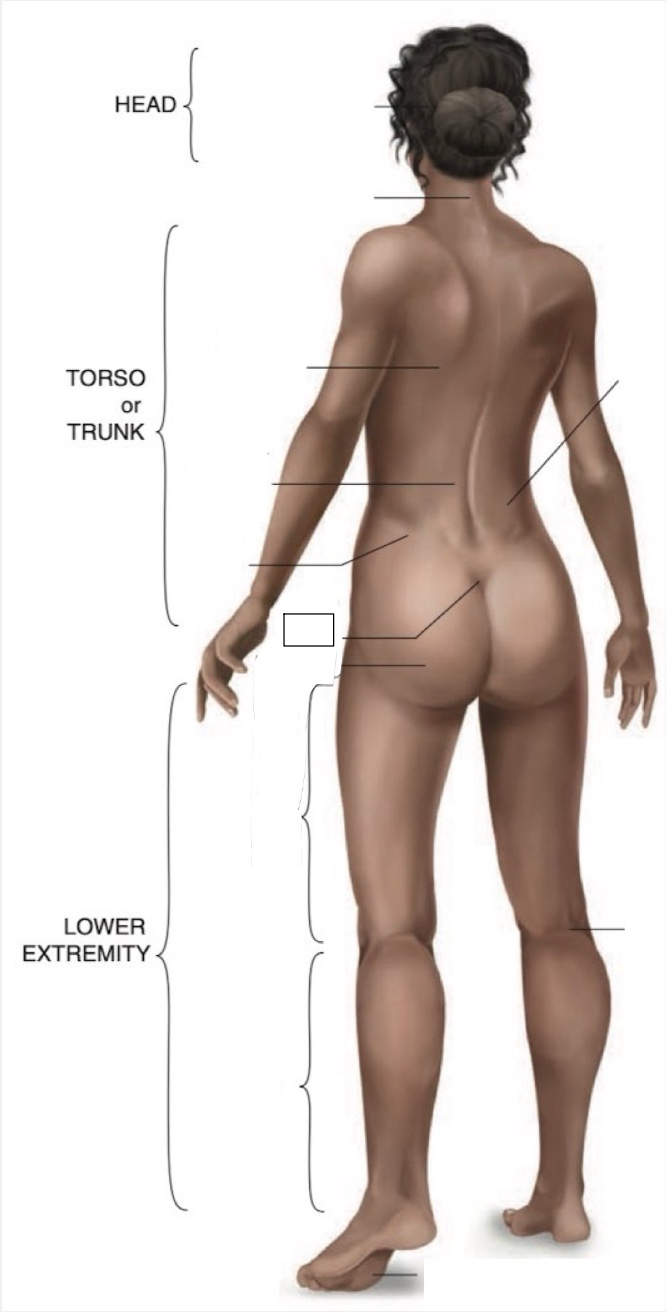

Occipital region

Cervical region

Inferior angle of scapula

Lumbar region

Iliac crest

Sacral region

Buttock

Flank